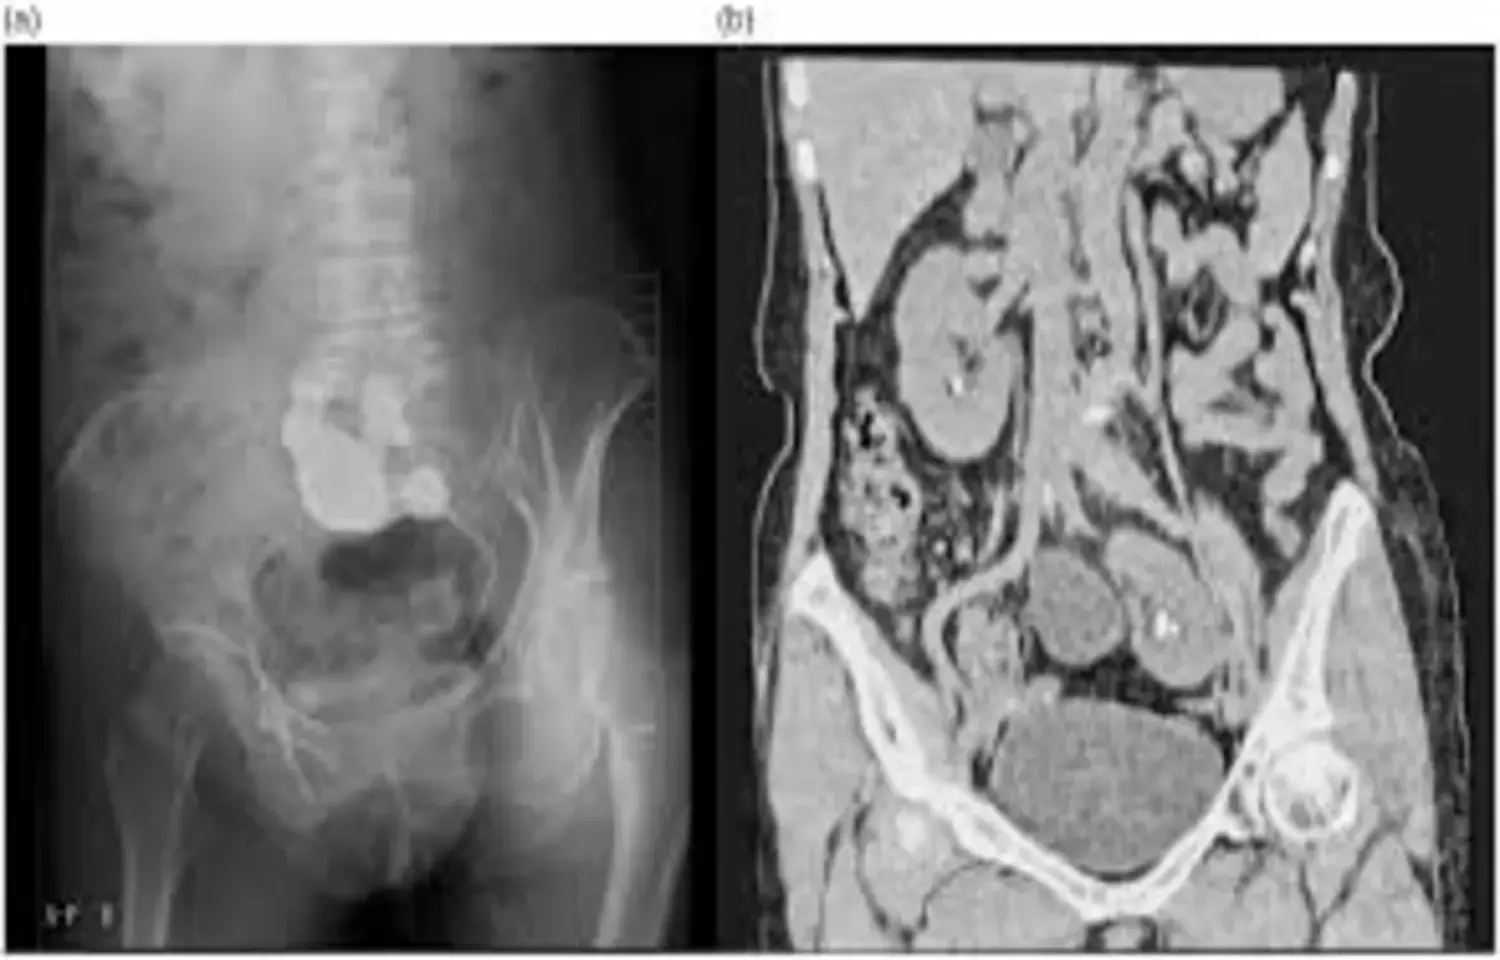

A study was done to evaluate the effectiveness and safety of current surgical modalities for nephrolithiasis in ectopic pelvic kidneys, a rare congenital anomaly with limited available evidence. A multicenter retrospective study was conducted across 11 high-volume international centers, including 45 patients with congenital pelvic kidneys who underwent flexible ureteroscopy, multimodal-guided percutaneous nephrolithotomy, and laparoscopic pyelolithotomy. Stone-free rate (defined as 0 mm), need for ancillary procedures, and complications (Clavien–Dindo) were assessed.

Results: Stones were classified as GUYS II in 51.1% of patients and GUYS III–IV in 48.9%. flexible ureteroscopy was the most common primary treatment (51.1%), followed by multimodal guided - PCNL (33.3%). Multimodal-guided PCNL achieved the highest stone free rate (86.7%) and the lowest requirement for ancillary procedures (OR 9.7; 95% CI 1.8–51 compared with other modalities). The overall final stone free rate for the cohort was 65.9% after a mean of 1.38 procedures per patient. Complications occurred in 13.3% of cases, with only one major event (Clavien-Dindo IVa).